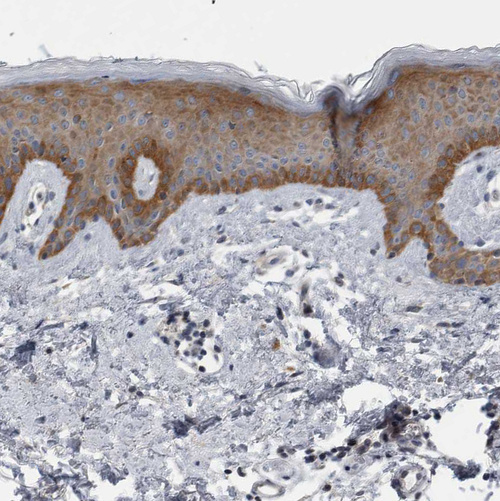

Immunohistochemistry analysis in human skin and skeletal muscle tissues using HPA023369 antibody. Corresponding FAM83G RNA-seq data are presented for the same tissues.